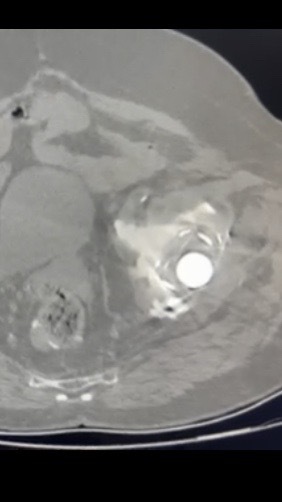

Τα περισσότερα εμφυτεύματα σήμερα έχουν παρόμοια σχέδια και σχήματα, αλλά ο γιατρός σας θα καθορίσει ποια σχέδια λειτουργούν καλύτερα για το σώμα σας. Αυτά τα εμφυτεύματα είναι κατασκευασμένα από κοβάλτιο χρώμιο ή τιτάνιο. Μια μεταβλητή που παραμένει ακόμα είναι η επιφάνεια φόρτισης. Η επιφάνεια φόρτισης είναι η σφαίρα, η κεφαλή και η επένδυση που προσκολλώνται στο μηριαίο στέλεχος, και το κυπέλιο, η το κοτυλιαίο εμφύτευμα που στερεώνεται στο οστό. Η κεφαλή μπορεί να αποτελείται είτε από μέταλλο (κράμα χρωμίου κοβαλτίου) είτε από κεραμικό και η επένδυση μπορεί να είναι από πλαστικό (πολυαιθυλένιο), μέταλλο ή κεραμικό. Η κεφαλή και η επένδυση μπορούν στη συνέχεια να χρησιμοποιηθούν σε διαφορετικούς συνδυασμούς και ονομάζονται για τον αντίστοιχο συνδυασμό επένδυσης κεφαλή (μέταλλο σε πολυ, κεραμικό σε πολυ, κεραμικό σε κεραμικό κ.λπ.).

Το 2023, τα περισσότερα χρησιμοποιούσαν επένδυση πολυαιθυλενίου με κεραμική κεφαλή, ενώ άλλοι συνδυασμοί χρησιμοποιούνται με μικρότερη συχνότητα. Μπορείτε να συζητήσετε αυτές τις διαφορές με τον χειρουργό σας για να προσδιορίσετε ποιο εμφύτευμα είναι καλύτερο για εσάς.